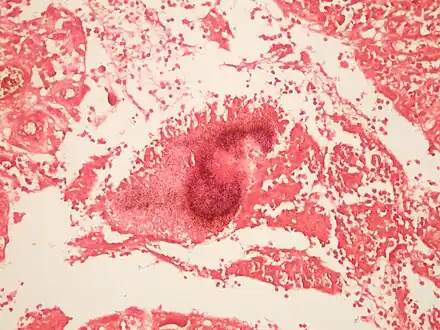

Contrast-enhanced magnetic resonance images showing contiguous spread of pulmonary actinomycosis to the spine.jpg.webp) Colony of Actinomyces surrounded by macrophages.. A Gram stain is needed to see the filamentous organisms. Large colonies of Actinomyces can appear macroscopically as yellow granules whch have been termed "sulfur granules".

Colony of Actinomyces surrounded by macrophages.. A Gram stain is needed to see the filamentous organisms. Large colonies of Actinomyces can appear macroscopically as yellow granules whch have been termed "sulfur granules"..jpg.webp) Thin Gram positive filamentous organisms seen at the periphery of the colony

Thin Gram positive filamentous organisms seen at the periphery of the colony.jpg.webp) Thin Gram positive filamentous organisms seen at the periphery of the colony (lower)

Thin Gram positive filamentous organisms seen at the periphery of the colony (lower).jpg.webp) Thin Gram positive filamentous organisms seen at the periphery of the colony (upper)

Actinomycosis Grocott's stain Actinomycosis Gram stain

Actinomycosis Gram stain